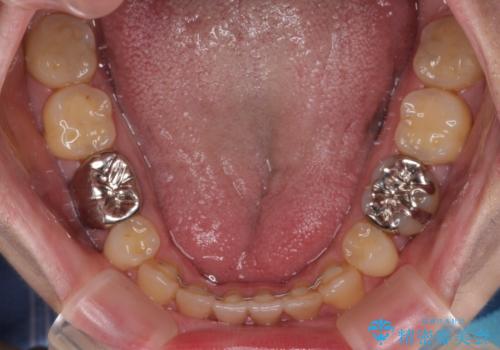

- 抜歯矯正の後戻りを気にして来院された患者様です。

舌の突出癖によるオープンバイトになり、前歯の叢生が後戻りしていました。

舌のトレーニングを行いながら、インビザラインを用いて矯正治療を行うこととしました。